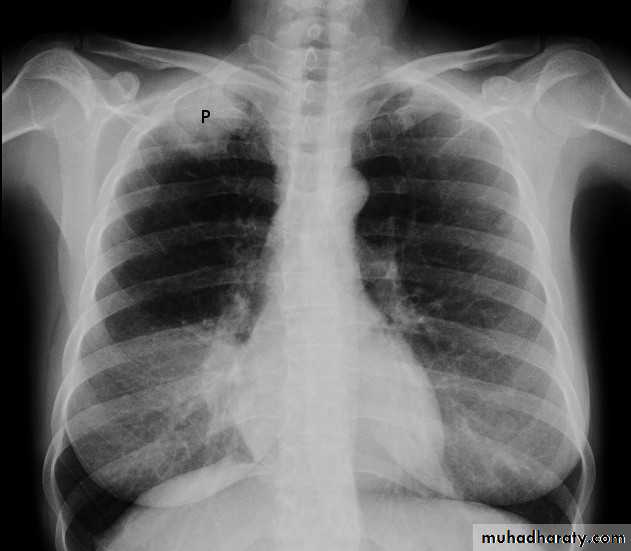

PneumothoraxX-ray pneumothorax

X-ray pneumothorax